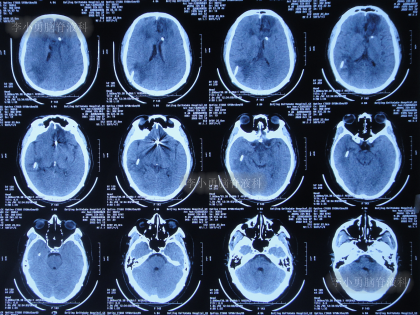

入院时头颅CT示脑室扩张,动脉瘤栓塞术后(图-11)。

图-11:入院时头颅CT

脑室外引流术后4天即2022年8月29日,患者出现意识差,查头颅CT示左侧脑室仍扩张(图-14)。

图-14:2022年8月29日头颅CT

当天给予了左侧脑室外引流术,术后当天查头颅CT示脑室内有2根管(图-15);术后脑脊液化验出真菌。

图-15:2022年8月29日术后头颅CT

2022年9月14日(住院治疗21天),体温变正常,查头颅CT示双侧脑室均变小(图-17)。

图-17:2022年9月14日头颅CT

2022年9月27日(住院治疗34天),患者出现意识差,查头颅CT示颞角扩张(图-18)。

图-18:2022年9月27日头颅CT

2022年10月12日(住院治疗49天),脑脊液真菌彻底消灭,查头颅CT示颞角缩小(图-20)。

图-20:2022年10月12日头颅CT

脑脊液各项化验均正常后于2022年12月14日(住院治疗112天),进行了脑室腹腔分流术(图-23)。

图-23:2022年12月14日头颅CT

2022年12月27日(李小勇脑脊液科治疗125天)康复出院,出院时:神清气爽,心情愉悦,走路基本正常,言语交流正常(图-24);出院时头颅CT示未见异常(图-25)。

图-25:出院时头颅CT